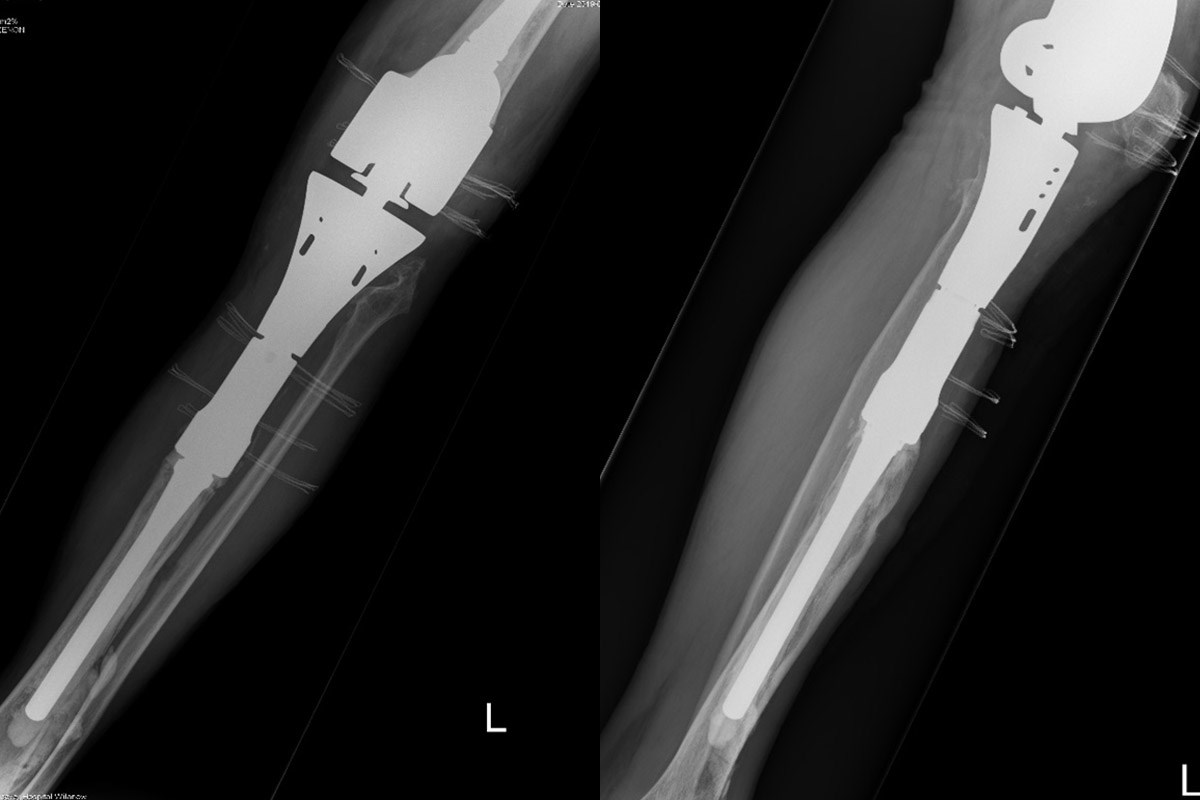

Dr hab. n. med. Ireneusz Babiak, dr n. med. Piotr Pędzisz oraz dr Jakub Janowicz zastosowali antybakteryjną powłokę podczas wymiany endoprotezy onkologicznej stawu kolanowego oraz 16-centymetrowego bliższego odcinka kości piszczelowej. Pacjent przed dwunastu laty w Stanach Zjednoczonych miał usunięty guz kości piszczelowej i wszczepioną endoprotezę poresekcyjną (tzw. megaprotezę), a później był reoperowany z powodu infekcji endoprotezy.

Z uwagi na fakt, że ten rodzaj endoprotezy jest szczególnie zagrożony zakażeniem, które z kolei jest bardzo groźnym powikłaniem takiej operacji rewizyjnej, zespół lekarzy z Kliniki Ortopedii Rehasport: dr hab. n. med. Ireneusz Babiak, dr n. med. Piotr Pędzisz i dr Jakub Janowicz zaplanował zastosowanie tej innowacyjnej powłoki, mającej chronić nową endoprotezę przed infekcją.